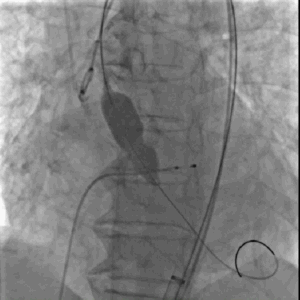

球囊扩张

瓣膜定位

快速释放瓣膜

瓣膜到位,患者突然心跳骤停,立即给予胸外心脏按压并快速释放瓣膜,之后继续胸外心脏按压,肾上腺素静推。

瓣膜完全释放,形态良好、无周漏

经过以上处理,患者心跳恢复、血压回升、术后压力阶差降至小于3-5mmHg,瓣膜形态良好,极少量瓣周漏,但患者随后出现持续性室性心动过速。